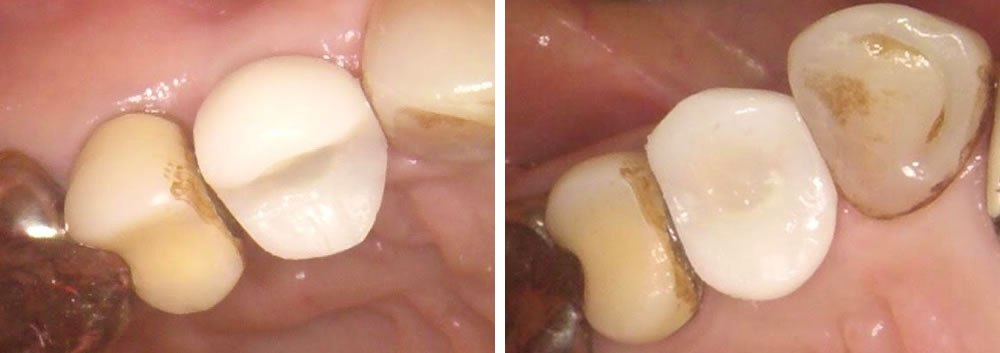

インプラント治療完了後の口腔内写真

インプラントと顎骨が結合するための待機期間を経て、3ヵ月で綺麗に上部の歯を作成する事ができました。